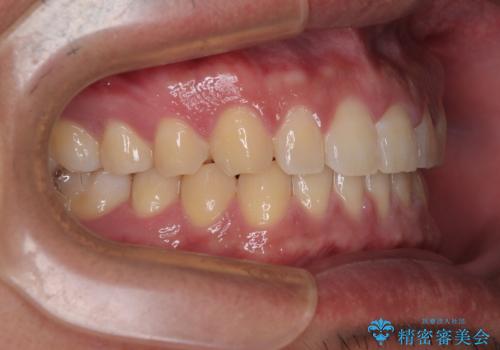

舌のトレーニングをしっかりと行ってくださったおかげで、順調に治療を終えることができました。

舌の突出癖が速やかに改善され、後戻りによるスペースは今のところ認められておりません。